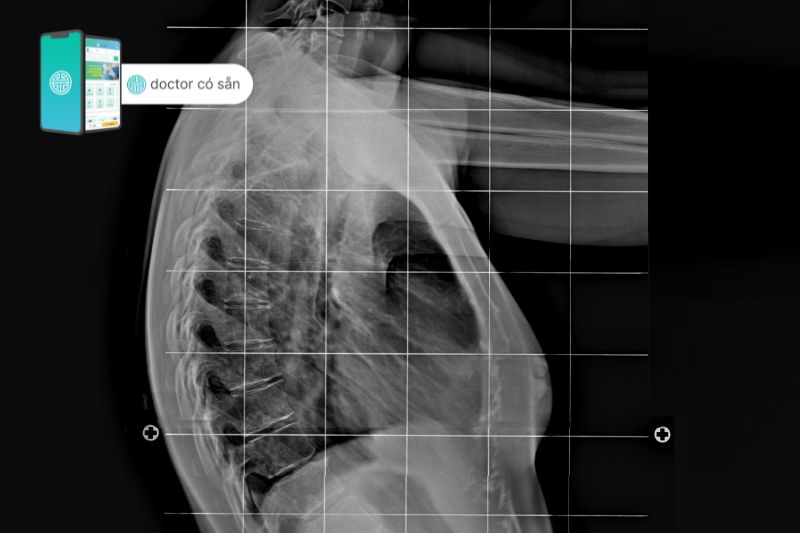

Xét nghiệm chẩn đoán cho trẻ em bị gù lưng thường là chụp X-quang để đo và đánh giá mức độ cong của cột sống. Việc đánh giá này sẽ giúp xác định phương pháp điều trị thích hợp cho trẻ.

- Chụp CT hoặc CAT (cắt lớp vi tính): Sử dụng kết hợp tia X và công nghệ để tạo ra hình ảnh cắt ngang của cơ thể với hình ảnh chi tiết của xương, cơ, mỡ và các cơ quan. Hình ảnh từ máy chụp CT chi tiết hơn hình ảnh được tạo ra bởi tia X.